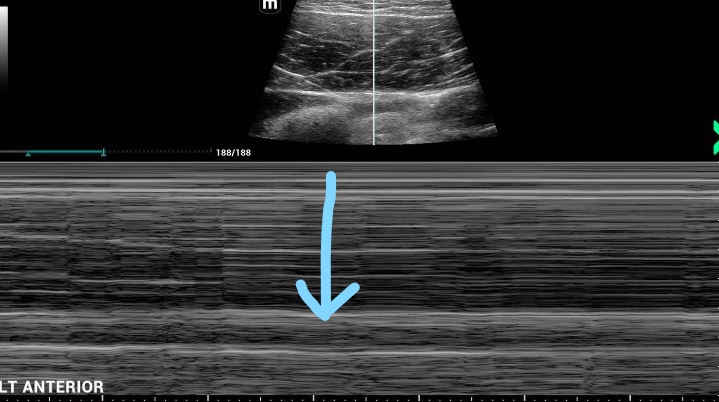

Left lung ultrasound M-mode

Interp: note the blue arrow again indicating the pleural line, and the "bar code" straight lines beneath this, which has the appearance of the superficial chest wall tissues above the pleural line. This indicates no lung sliding and confirms no lung is adherent to the chest wall at this site, making percutaneous chest tube placement safe